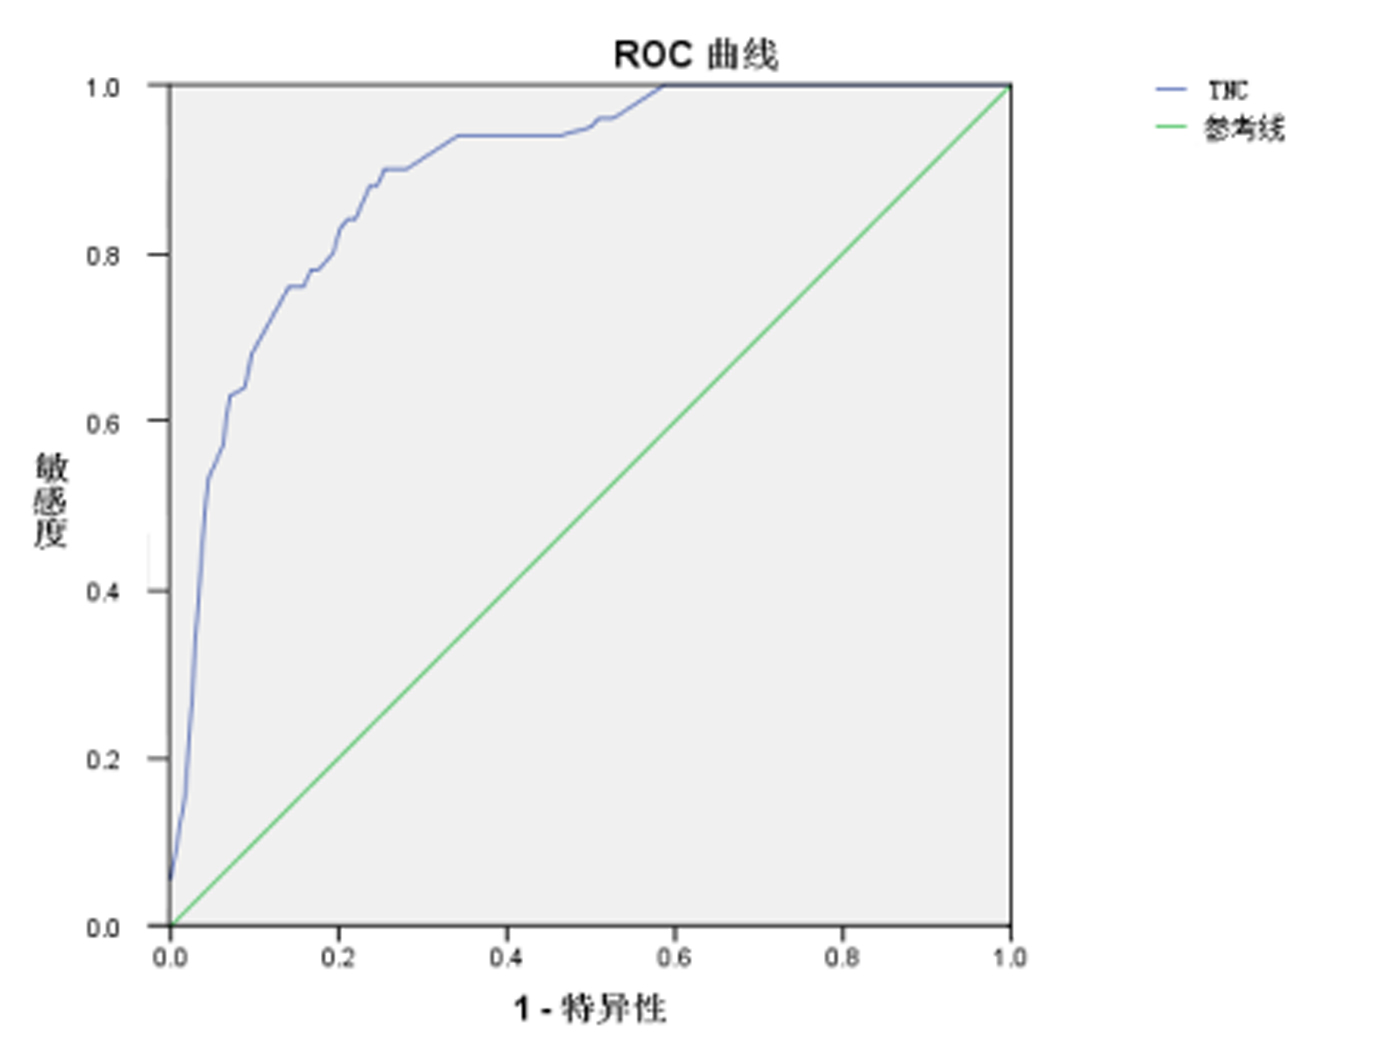

图 3为PQ中毒患者血清TNC的ROC曲线,对预测PQ中毒患者出现急性肺损伤和死亡,血清TNC曲线下面积(AUC)为0.895,急性PQ中毒患者根据血清TNC预测预后的截断值为41.9 ng/mL,表明若血清TNC浓度大于41.9 ng/mL则提示预后不良,其敏感度为84%,特异度为80%,Youden指数为0.64。

| 图 3 首诊血清TNC浓度受试者工作特征曲线 Fig 3 ROC of serum TNC level on admission |

依据急性PQ中毒患者的临床特点,本研究选取了首诊和中毒后72 h的肺部CT影像学和首诊和来诊72 h实验室生化检查指标进行比较分析。结果发现入院首次常规检查结果中,只有尿PQ浓度定量、动脉血Lac、PaCO2组间差异有统计学意义,而决定预后最关键的因素服毒量[16],却因受到患者的主观因素影响,无法用作定量的判断标准,只能作为大致参考。首诊尿PQ浓度虽然组间比较有差异,但其受院外行洗胃和血液净化等治疗、来诊距服毒时间间隔以及膀胱存留尿液量等因素影响[17-18],对评估预后也存在一定局限性。来诊72 h的最差生化检查结果中LPSmax、AMSmax、PaO2min、PaCO2min、Lacmax组间比较差异有统计学意义,同时肺部影像学出现明显差异。但作为早期肺损伤评估指标,显然在时间上均不具备优势。进一步Logistic多因素回归分析发现入院首次血清TNC浓度是急性PQ中毒患者预后的独立危险因素,不受服毒后就诊时间、来诊尿PQ浓度等因素影响,AUC为0.895,敏感度为84%、特异度为80%,cut-off值为41.9 ng/mL,表明若入院首次血清TNC浓度高于41.9 ng/mL,则患者急性肺损伤及肺纤维化进展较快,28 d死亡风险较高。